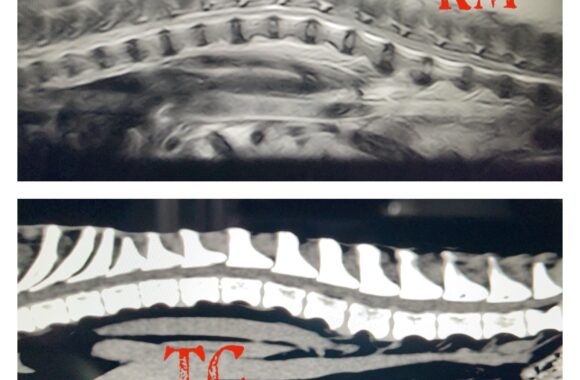

Il Servizio Tac Veterinaria a Portici

Attualmente l’unica clinica veterinaria di Napoli e provincia che ha a disposizione una TAC Multistrato da 128 strati in struttura, ultra veloce (total body in meno di 15 sec.), con refertazione in 24h/48h.

Vuoi sapere come funziona la TAC?

Che differenza c’è tra TAC e Risonanza Magnetica?? leggi l’articolo